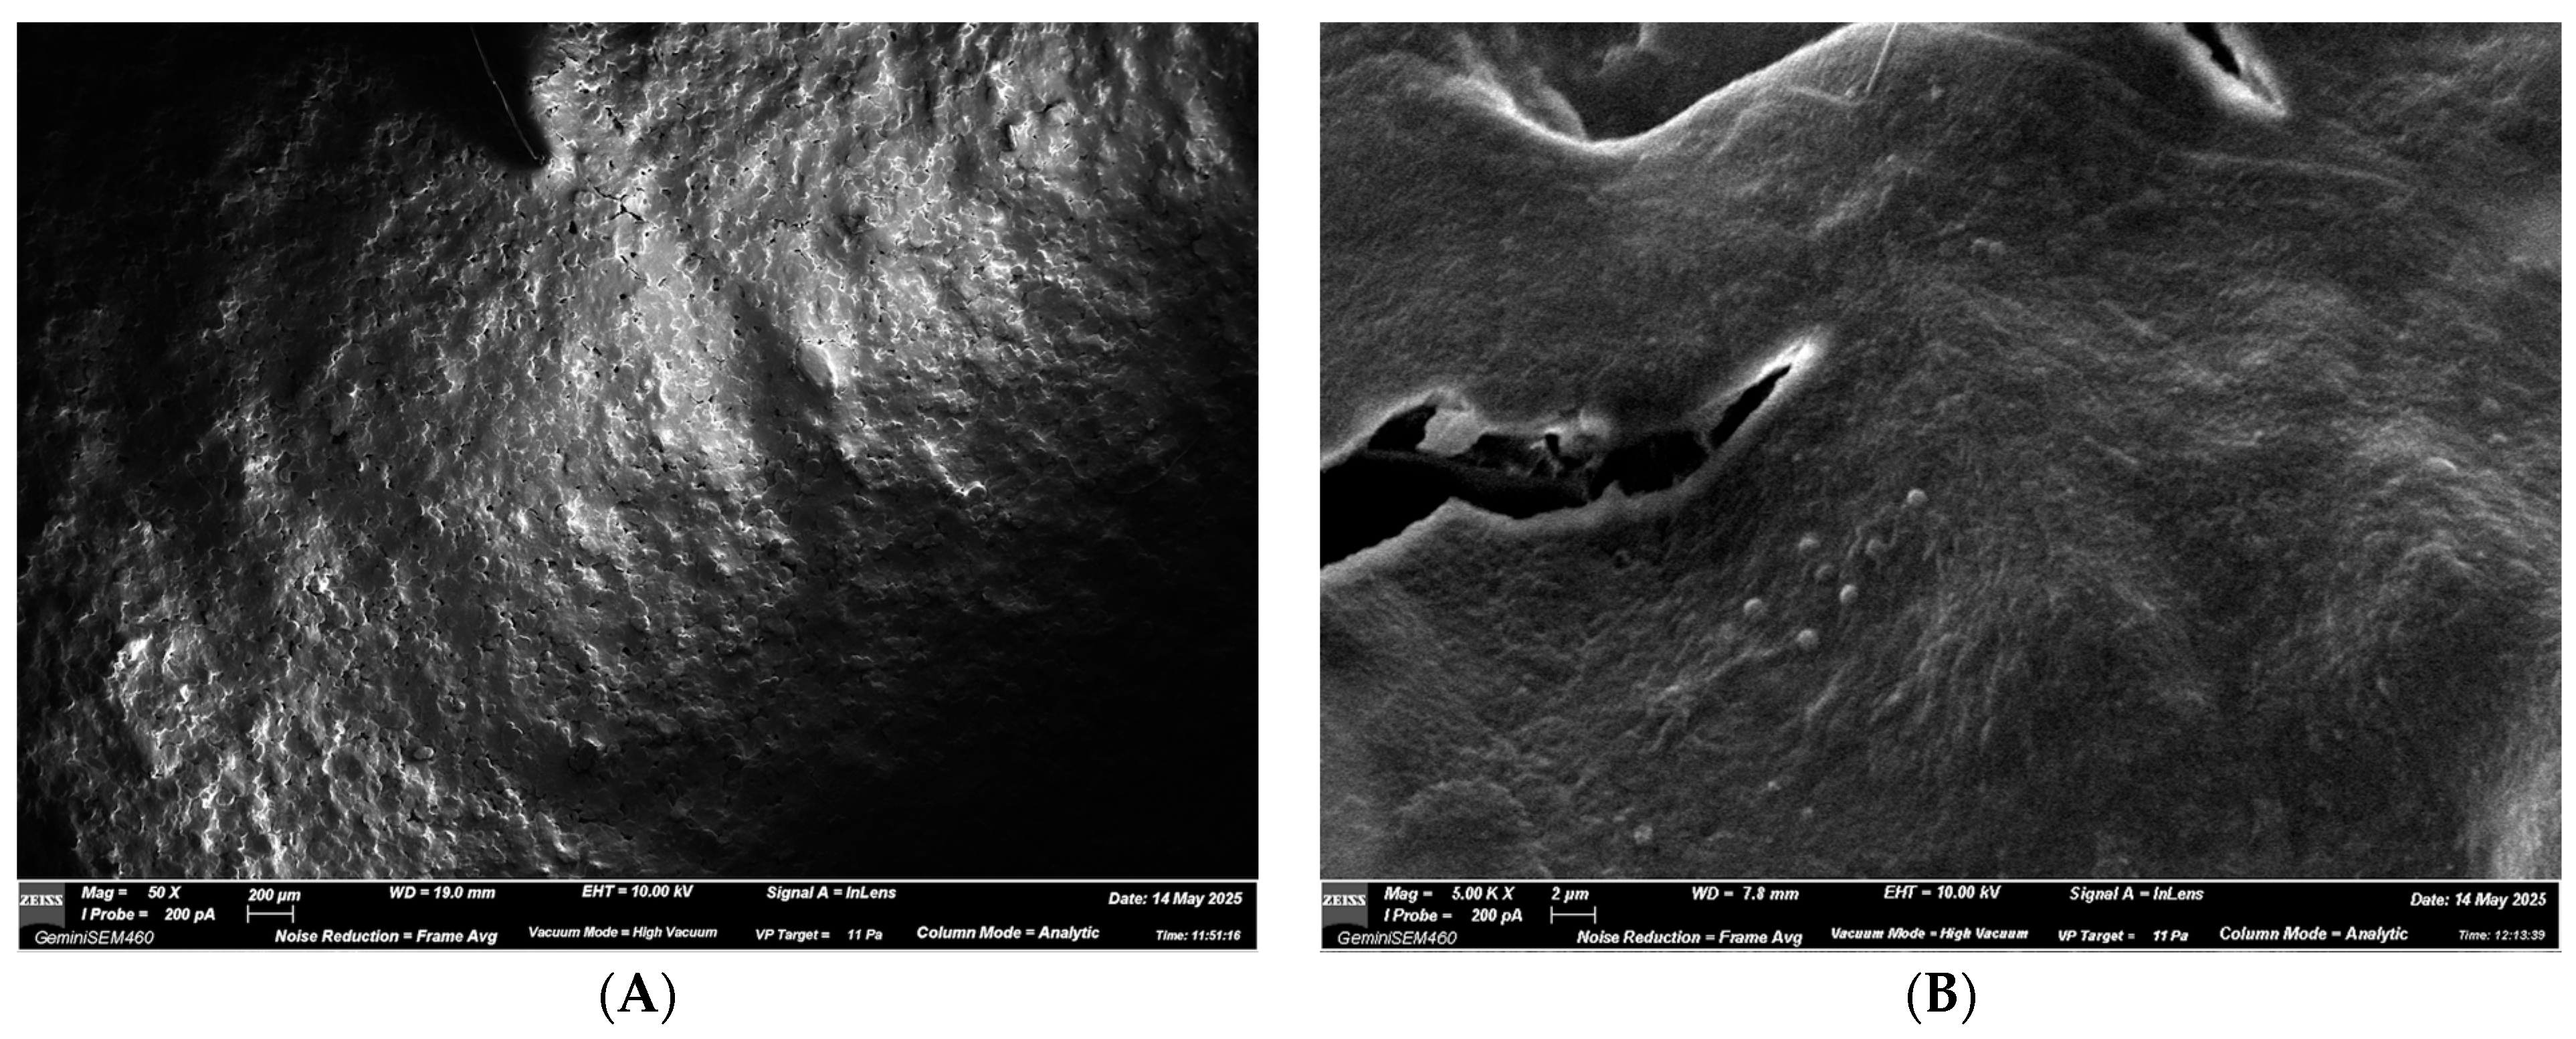

3.2.1. ALIGNER A—NEW Aligner

- Aligner A (new control);

- NEW aligner (unused);